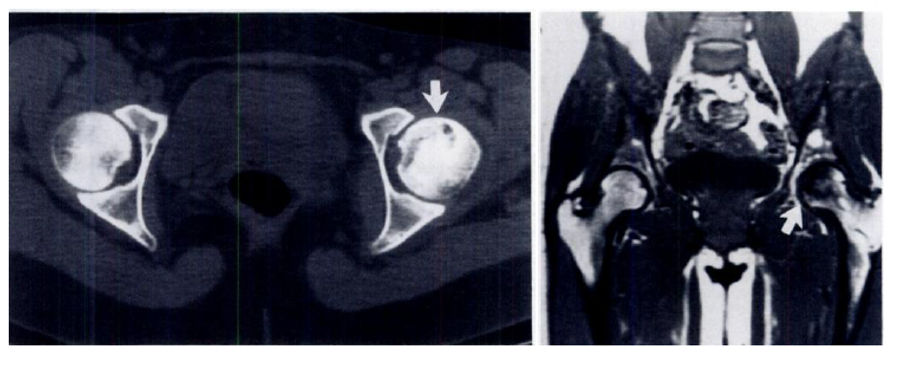

Left: CT showing a dark region of avascular necrosis in a characteristic "crescent-moon" shape (white arrow...don't worry, this wouldn't jump out at me either. Radiologists are very good at their jobs). Right: An MRI showing the same patient's avascular necrosis (white arrow). Images via Mitchell, Kundell, et al.